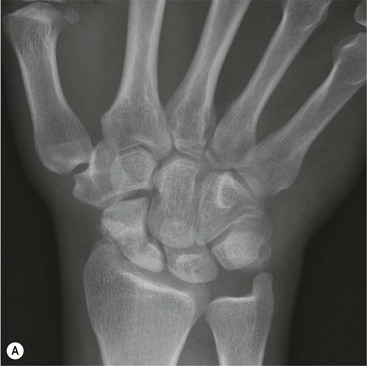

The scapholunate ligament is most frequently involved. Radiographs may show scapholunate diastasis (>3 mm). The lunate demonstrates dorsal rotation on lateral views and volar rotation of the scaphoid. This results in an increase in the scapholunate angle (>60°) known as dorsal intercalated segment instability (DISI) (Fig. 46-27). A DISI deformity of the carpus may also be associated with fractures of the scaphoid.